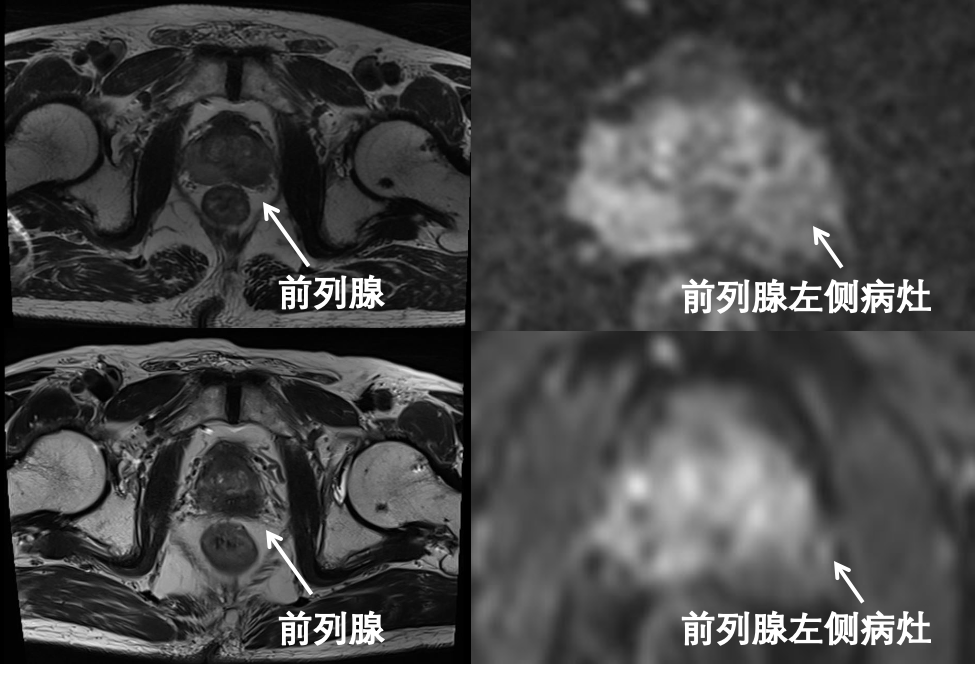

5个月前,71岁的王先生(化名)在体检时发现前列腺特异抗原(PSA)水平异常升高,遂慕名前往中国医科大学附属第一医院寻求诊治。泌尿外科张墨教授接诊后为其完善相关检查,其PSA水平为69.40ng/ml,远超正常范围(0-4ng/ml);前列腺多参数磁共振结果显示前列腺左侧叶外周带异常信号影,范围约2.6*1.4cm,左侧精囊可疑受侵,PI-RADS评分为5分,高度提示恶性病变可能;磁共振/超声融合前列腺穿刺活检术病理结果为前列腺腺泡腺癌,Gleason评分为4+3=7分,且双侧前列腺叶均存在癌组织浸润。综合各项检查结果,患者符合高危局部进展期前列腺癌的诊断标准。

经过阶段性系统治疗后,结果显示治疗方案疗效显著:PSA水平已由初始的69.4ng/ml迅速降至0.18ng/ml。复查前列腺磁共振对比分析显示,原发病灶范围缩小至1.0*0.8cm,且前列腺整体体积亦见明显缩小。影像学降期与生化指标的同步改善,充分表明了患者对当前用药方案反应良好,为后续根治手术的实施创造了有利条件!

经新辅助内分泌治疗后,MRI显示患者前列腺及肿瘤体积明显缩小